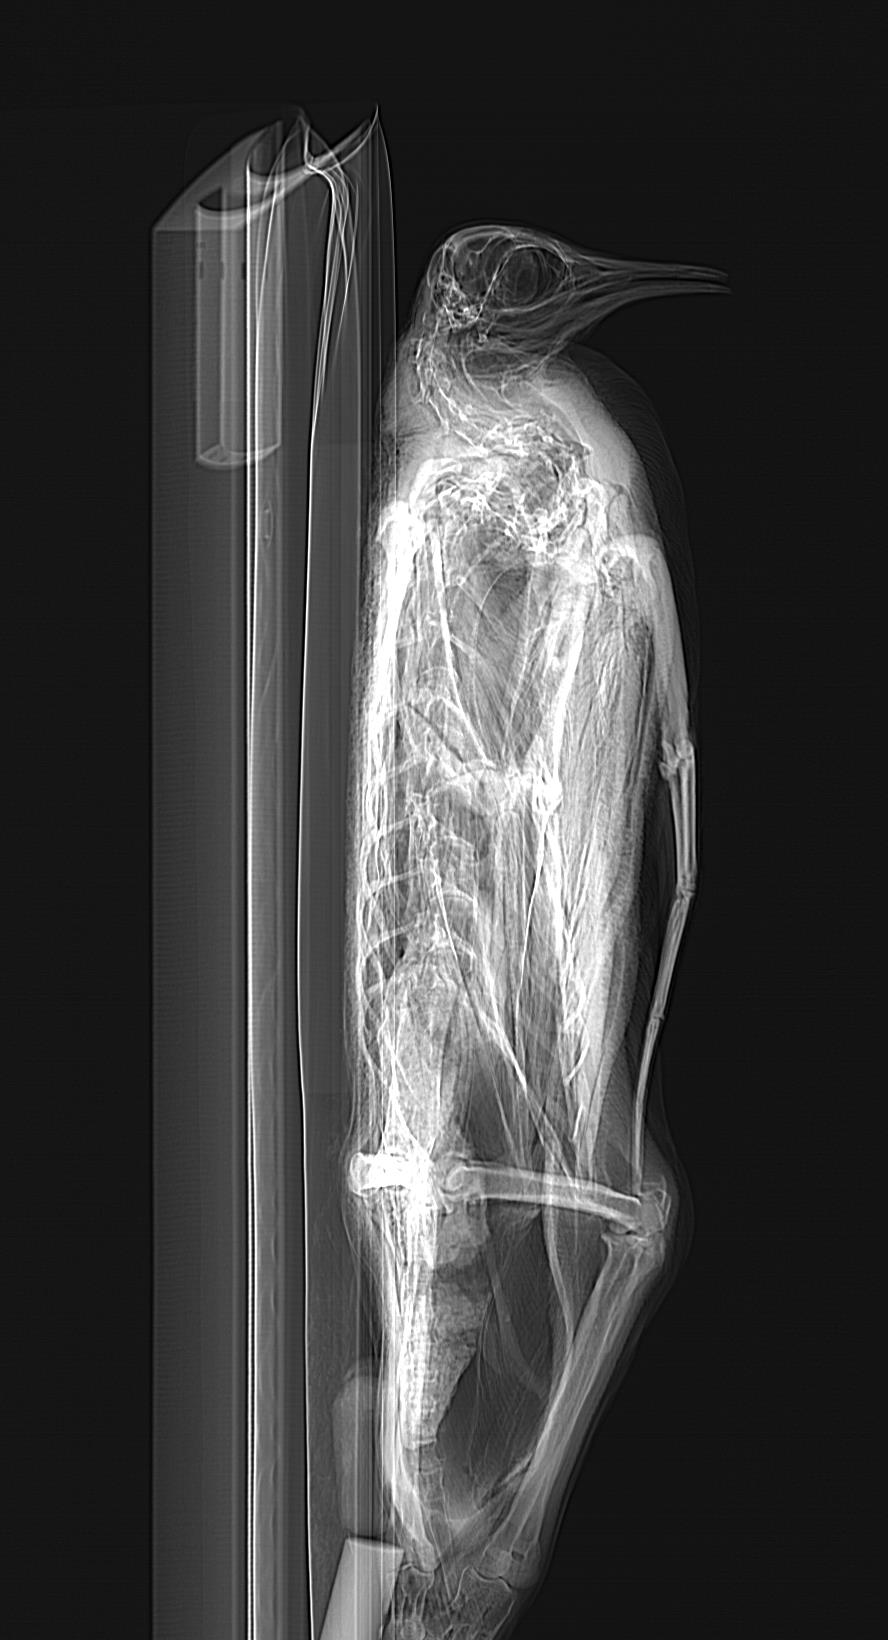

And this handsome Emperor penguin, going through the Equine Imaging Centre’s CT scanner as I do my usual routine of (1) get cool critters, (2) barrage them with radiation to peek inside:

Because I love the CT scan images of these penguins so much (their skeletons are awesome and bizarre!), I’ll share the pilot scans of the best ones now: